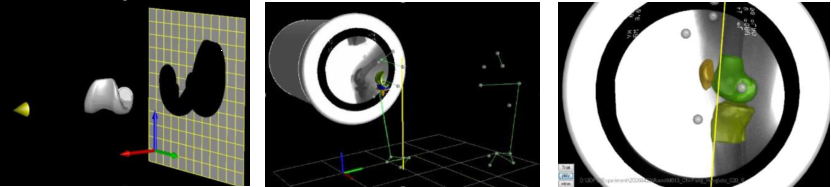

(3) Imaging Tracking Technique 影像追踪技术

Fluoroscopic Tracking Technique (2D-3D registration) 荧光检查追踪技术(2D-3D配准)

图注:开发医学影像技术评估活体髋与假体关节功能

图注:开发利用3维数字化骨骼模型与2维动态X光配准的技术,实现非侵入式的精准在体关节运动测量